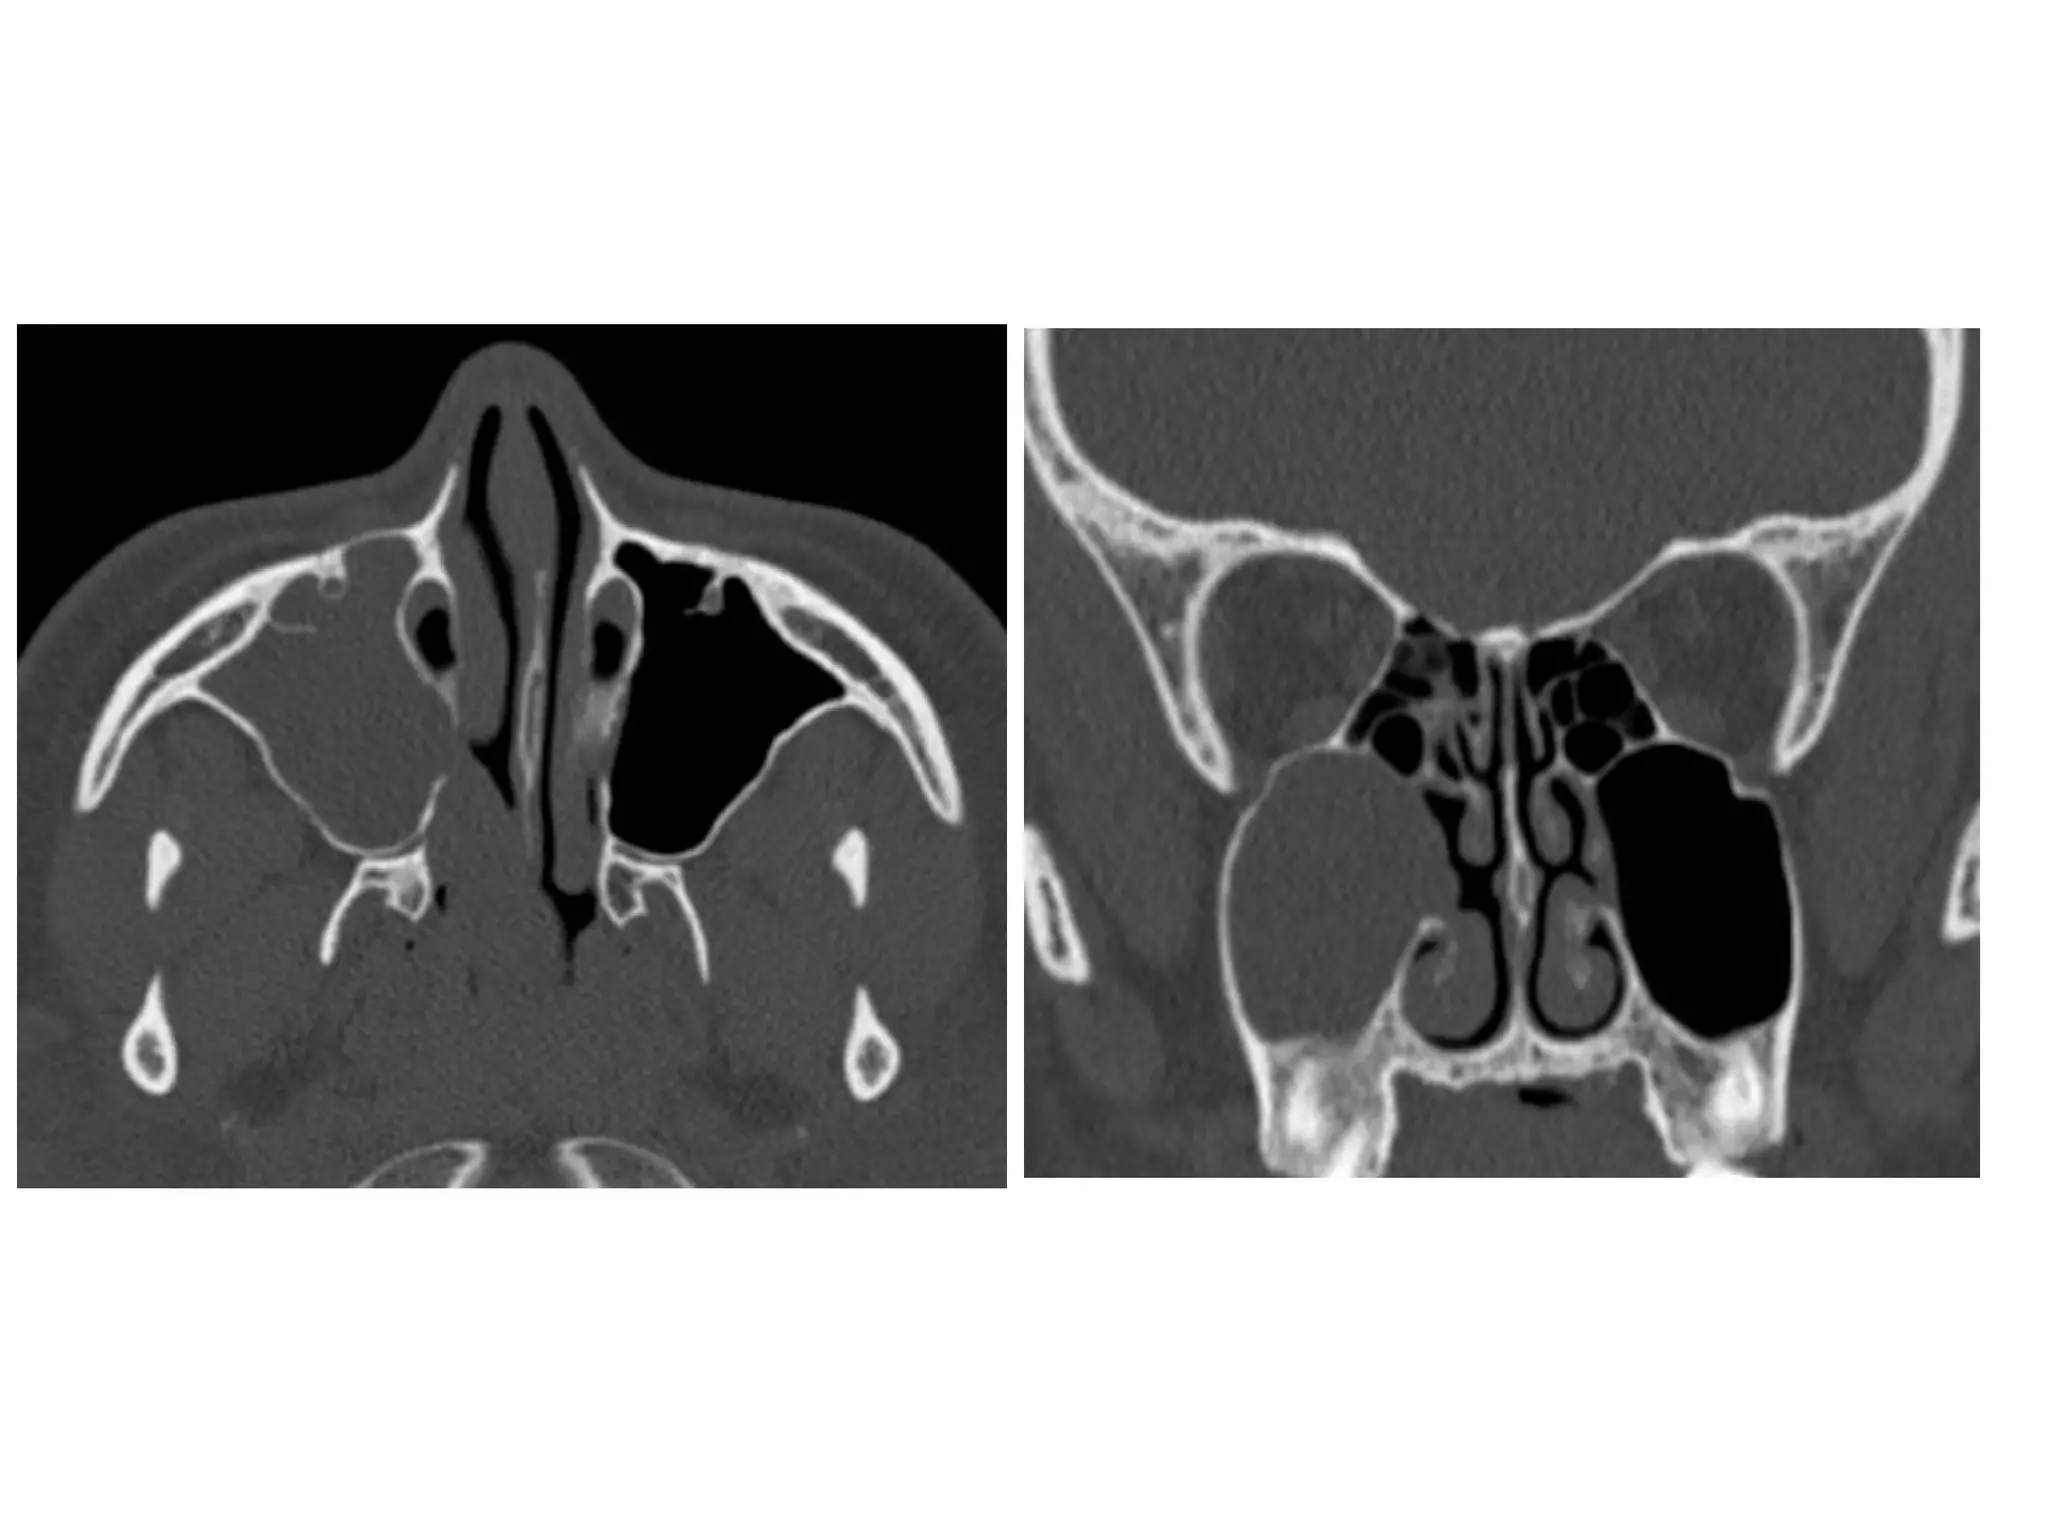

Antrochoanal polyp, axial (A) and coronal (B) CT show complete

opacification of the right maxillary sinus with extension into the right

middle meatus and inferior aspect of the right nasal cavity, there is

thickening of the sinus walls but no sinus expansion